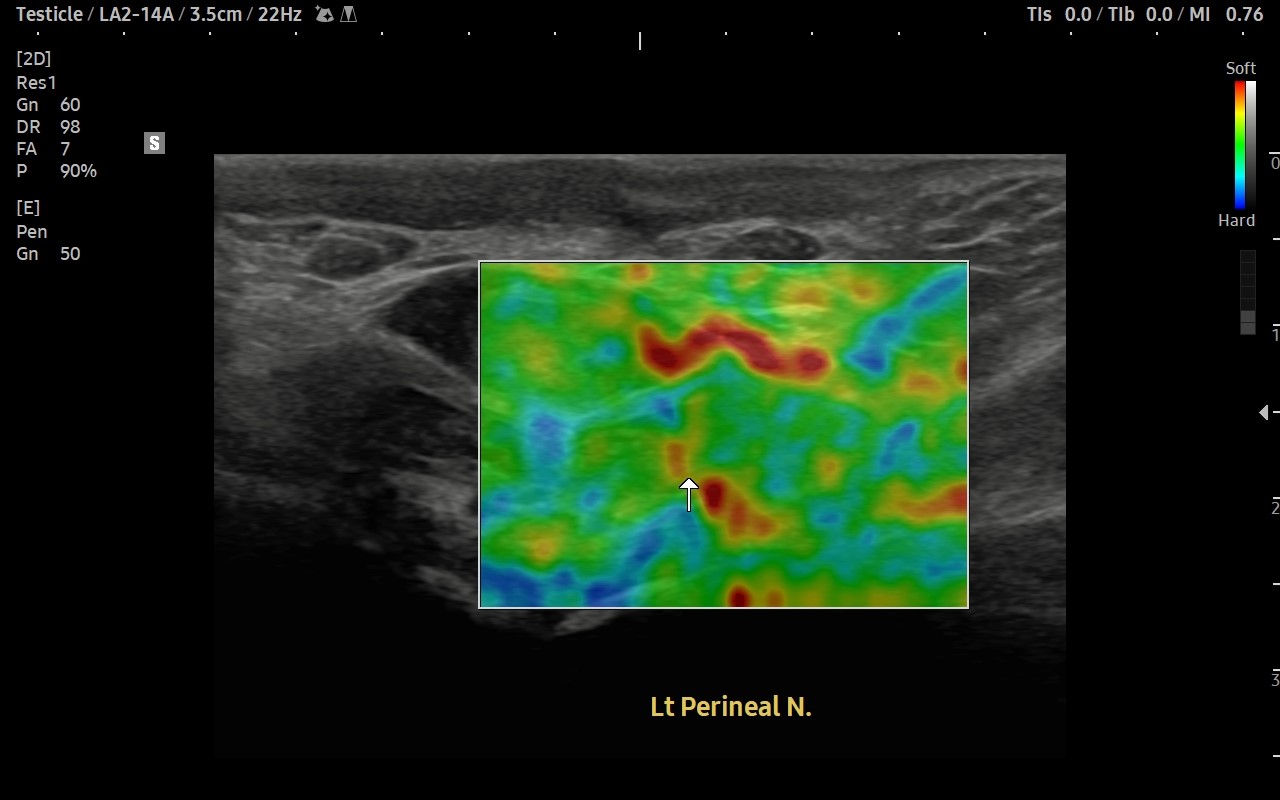

[치료 전]

[치료 후]

- 치료횟수 : 30 회